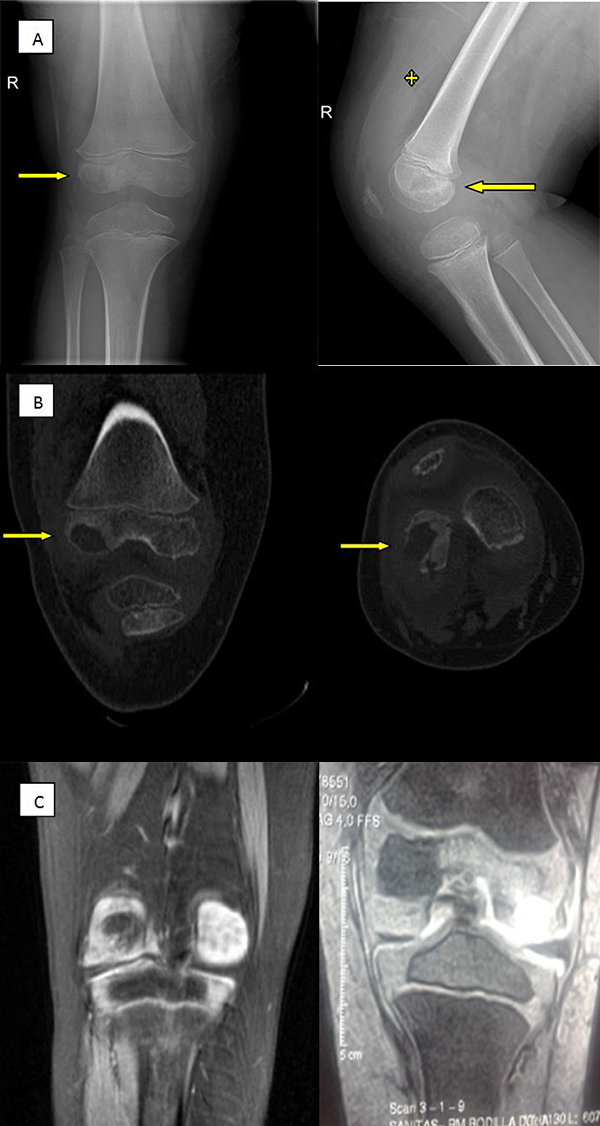

La radiografía de rodilla evidenció una lesión ósea lítica de aspecto redondeado en condilo femoral externo junto a un aumento de partes blandas y derrame articular (fig. 1A). La tomografía axial computarizada (TAC) objetivó una lesión de 15x13x12 mm en el cóndilo femoral externo que contactaba con las partes blandas adyacentes a través de pequeños canales sugestivos de cloacas, y que en la región posterolateral mostró una colección/absceso 9x10 mm en el contexto de una posible osteomielitis subaguda (fig. 1B). En la resonancia nuclear magnética (RNM) que aporta al ingreso, se observa lesión lítica osteocondral epifisaria en cóndilo femoral externo con cavidad de más de 1 cm y edema perilesional sugerente de osteomielitis aguda sin descartar origen tumoral (condroblastoma) (fig. 1C).

Figura 1: A) Rx rodilla derecha frente a la izquierda y lateral a la derecha. Flechas indicando la lesión lítica y asterisco mostrando derrame articular en fondo de saco sub cuadricipital. B) Imagen coronal de TAC con lesión lítica en cóndilo femoral externo a la izquierda y proyección axial a la derecha que muestra comunicación articular con aumento de partes blandas (detalle flechas). C) Imagen coronal RNM a izquierda y derecha que muestra hiperintensidad por mayor captación en cavidad acompañado de edema perilesional.